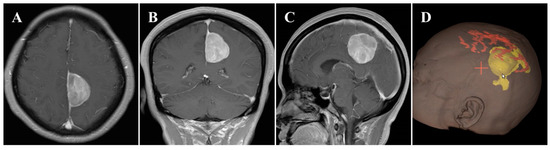

2.3. Postoperative Course

The surgery was uneventful, and the pathological diagnosis was FM, WHO grade I (Figure 3). After surgery, the patient had an uneventful recovery and was discharged with no neurological deficit. The initial clinical follow-up was performed 6 months after surgery, at which point, MRI suggested that the compressed cerebral cortex had returned to its normal form (Figure 4). After 6 months of follow-up, subsequent follow-up visits were performed at yearly intervals or more frequently when indicated. During the 24-month follow-up, the patient’s condition remained favorable, with no tumor recurrence.

Figure 4.

Postoperative contrast-enhanced MRI images. (A–C) Six months after surgery, MRI indicated regained parenchymal normal morphology. Axial (A), coronal (B), and sagittal (C) images.

Noteworthily, in this case, there were two critical draining veins above the tumor, which increased the difficulty of tumor resection. However, we successfully removed the tumor using the endoscopic ipsilateral interhemispheric approach without any venous complications during or after surgery. Additionally, the presence of ipsilateral brain edema can narrow the entry corridor, representing a key concern of the ipsilateral interhemispheric approach. However, this concern can be overcome by using the gravity-assisted technique to gain more operating space, which is sufficient to allow safe and effective removal of the tumor using the endoscopic approach [6]. In this case, the main considerations for the use of the retractor were the presence of two critical draining veins above the tumor and the absence of severe ipsilateral brain edema. Gravity-assisted lateral positioning may increase tension in the veins, leading to injury, while the retractor is more controllable to keep brain retraction to a minimum. In other situations, such as the presence of severe ipsilateral brain edema or the absence of interference of draining veins, we would implement the gravity-assisted technique to extend the lateral corridor diameters. In the current case, postoperative MRIs showed that the overlying eloquent cortex returned to its original morphology (Figure 4).